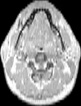

Visible Human male: Sectio transversalis 1198

CT

NMR

Pd T1 T2